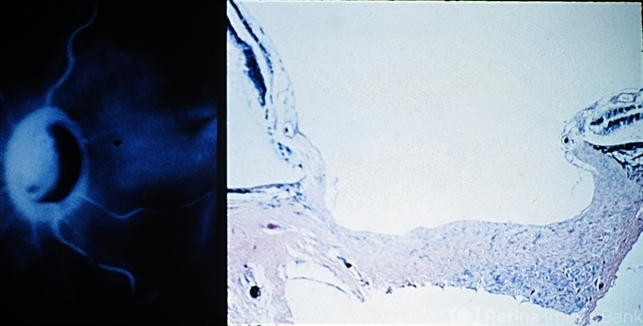

- Primary open-angle glaucoma. The macroscopic (left) and histologic (right) appearance of a deeply cupped optic nervehead is shown (right view, PAS x16).